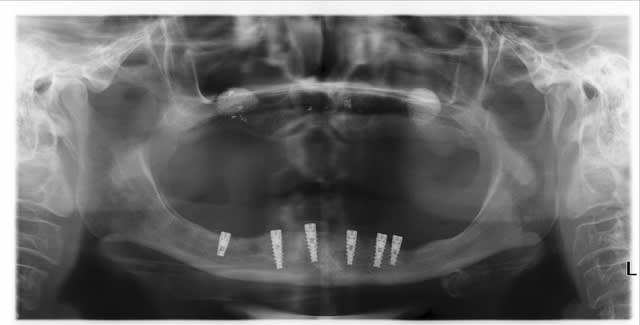

Il y a 6 implants à la mandibule , 2 sinus ont déja été réalisés et il va y avoir 8 implants maxillaires .

ce qui est bizarre c'est les niveaux osseux en bas par rapport aux implants:

c'est des juxta osseux ou des supra car entre la gauche et la droite c'est pas trop ça

les implants sont mal posés, avec +ou- de périimplantite, 2 voir 3 sont dans le NDI...bref: un beau cas d'école...de ce qu'il ne faut pas faire...

Mon préféré c'est l'implant en 46! elle ne t'as pas demandé pourquoi l'anesthésie n'était encore terminée ?

Ma première réflexion a été identique a celle de Chicot : ce sont des implants censés etre juxta osseux mais placés comme des transgingivaux et laisses enfouis sous la muqueuse. L implant 36 a une spire a nu et l implant 46 semble effectivement en rapport intrigant avec le ndi...

Effectivement le sinus lift gauche est très verticale. D' autre part les densités ne sont pas énormes.

pour la marque des implants...je dirais alphabio...très probable...ou AB dental...

les implants sont juxta (apex)ou tout simplement lingualés vis a vis de V3

j'avoue que l'implant en 46 sans paresthesie me laisse pantois .

A mon avis +1 pour alphabio mais ne touche pas ...........